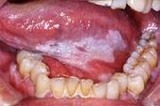

要旨:1.前癌病変 (白板症、紅板症、口腔扁平苔癬)

2.早期癌 (口腔扁平上皮癌、小唾液腺癌)

3.全身疾患で口腔内に症状を現す病変(尋常性天疱瘡、類天疱瘡、口腔カンジダ症)